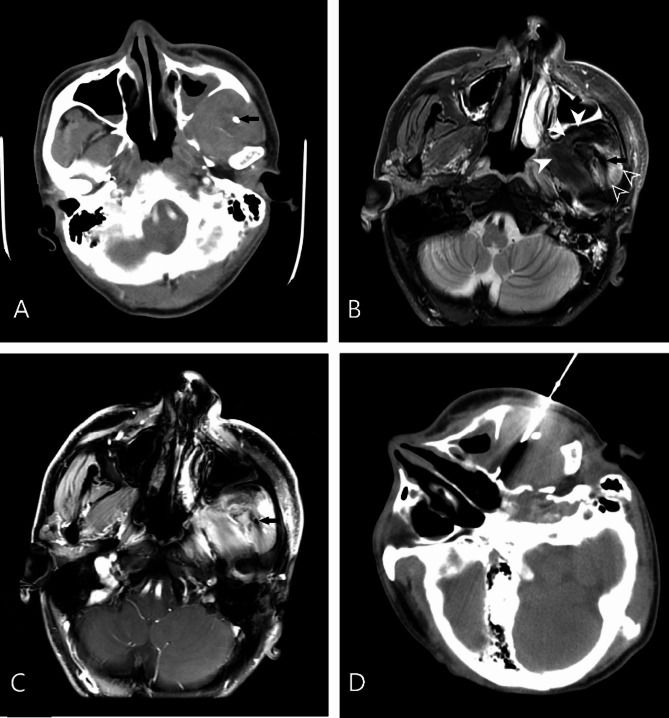

目的:舌骨上深部头颈部病变的病理诊断是重要的,组织取样需要平衡最小的侵入性和准确性。本研究的目的是评估ct引导下核心针活检(CNB)对舌骨上深部头颈部病变的诊断准确性和诊断失败相关因素。方法:回顾性分析204例ct引导下CNB患者的临床资料。ct引导下CNB采用18g同轴活检针进行病理诊断。病变诊断的准确性通过活检结果与手术标本的比较或根据治疗效果和6个月以上的临床随访来计算。通过卡方检验和程序特征和病变特征的logistic回归来确定与活检失败相关的因素。结果:所有204例标本均可用于组织学诊断,未发生立即或延迟的严重并发症。诊断敏感性为89.2%(141/158),特异性为97.8%(45/46),总体准确率为91.2%(186/204)。病变边界不清或术前诊断成像是诊断失败的潜在因素。结论:ct引导下的CNB是原发性舌骨上深部头颈部病变及颅底病变的有效组织诊断方法。值得注意的是,边缘不明确的病变和不理想的术前成像是导致诊断失败的潜在因素。具体来说,对于边界不清的病变,病变的范围难以划定,建议术前使用磁共振成像进行评估,以提高病变边缘的清晰度,从而有可能提高诊断的准确性。

Purpose: Pathological diagnosis is important for the treatment of deep suprahyoid head and neck lesions, and tissue sampling needs to balance minimal invasiveness and accuracy. The purpose of this study was to evaluate diagnostic accuracy and factors associated with diagnostic failure of core needle biopsy (CNB) with CT-guided in deep suprahyoid head and neck lesions.

Methods: The records of 204 patients who underwent CT-guided CNB were retrospectively reviewed. CT-guided CNB was conducted for pathological diagnosis with the use of 18-G coaxial biopsy needles. Diagnostic accuracy for the diagnosis of lesions were calculated by comparing the biopsy results with the operative specimen or based on treatment response and clinical follow-up more than 6 months. Factors associated with biopsy failure was identified by chi-square test and logistics regression of procedure characteristics and lesion features.

Result: All 204 specimens were deemed adequate for histological diagnosis, with no immediate or delayed severe complications encountered. The diagnostic performance showed a sensitivity of 89.2% (141/158), specificity of 97.8% (45/46), and overall accuracy of 91.2% (186/204). Respectively, lesions with poorly defined margins or pre-procedural diagnostic imaging were the potential factor for diagnostic failure.

Conclusion: CNB with CT-guidance is an effective procedure for tissue diagnosis of patient with primary deep suprahyoid head and neck lesions and skull base lesions. Notably, lesions with poorly defined margins and suboptimal pre-procedural imaging emerged as potential factors contributing to diagnostic failure. Specifically, for lesions with indistinct boundaries-wherein the extent of the lesion is difficult to delineate-pre-procedural assessment using magnetic resonance imaging is recommended to enhance the clarity of lesion margins, thereby potentially improving diagnostic accuracy.